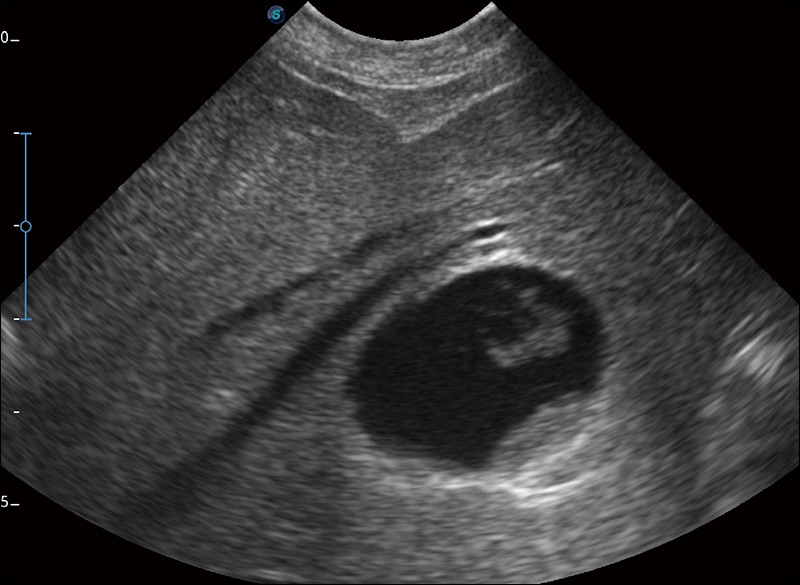

实时宽景成像

可实时观察感兴趣区域和病变位置

穿刺针增强

高清显示穿刺进针情况